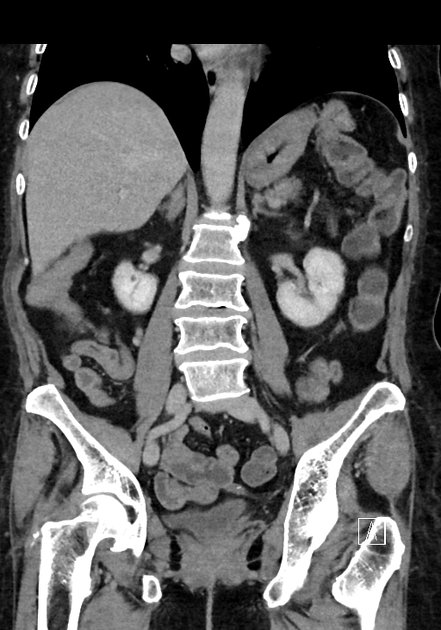

CT Bleeding Study

4 views

Jan 20, 2025

A patient presents with acute hypotension and hematochezia. An estimated 2L of blood loss was recorded in the ED. The patient was referred to general surgery. The bleeding stopped, and the patient remained hemodynamically stable. A colonoscopy was arranged. CT findings suggest an unusual cause of lower gastrointestinal bleeding. Based on the provided CT scan and case history, what is the most likely diagnosis?

Correct answer is Appendiceal hemorrhage due to angiodysplasia